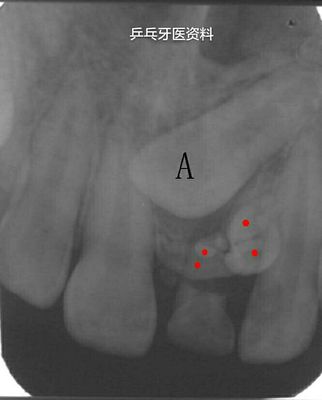

X线检查确诊前牙区有2颗多生牙